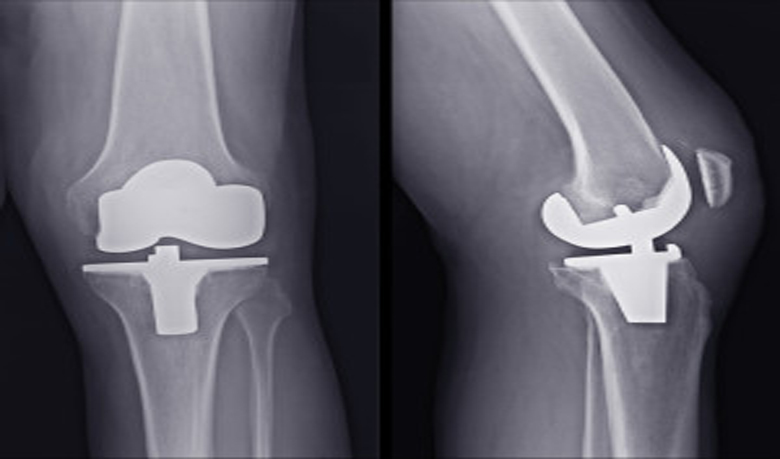

কোন কারণে হাড়ে ব্যথার পর যদি তা প্রচুর পরিমানে ফুলে যায়, নড়াচড়া করলে প্রচন্ড ব্যথা অনুভুত হয়। তা’হলে হাড় ভাঙতে পারে। যদিও শুধু এ লক্ষণ দেখে নিশ্চিত হওয়া যায় না। এজন্য দরকার এক্সরে। এক্সরে করলে নিশ্চিত হওয়া যাবে হাড় ভেঙেছে কি না।